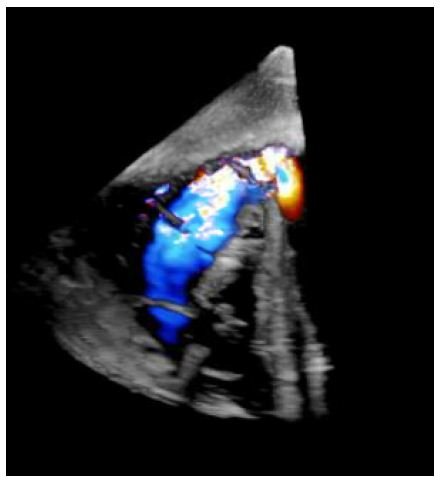

The diagnosis of Ebstein’s anomaly of the tricuspid valve by the simultaneous recording of intra-cavitary electrocardiograms and pressures across the tricuspid valve was a well-established technique as of the mid-1970s. However, such a method has not been used to diagnose Ebstein’s anomaly of the left atrioventricular valve in patients with CCTGA. We made simultaneous intra-cavitary electrocardiographic and pressure recordings across the left atrioventricular valve simultaneously (Figure 1) in a 13-month-old infant with angiographically confirmed CCTGA and left atrioventricular valve insufficiency (Figure 2) [2]. These recordings were similar to those obtained in classic cases of Ebstein’s anomaly of the tricuspid valve.

In the discussion section, we reviewed the historical aspects of CCTGA, described the anatomy and typical angiographic findings of the condition, and pointed out the frequent association of Ebstein’s type of malformation of the left-sided, morphologic tricuspid valve in CCTGA, and the usefulness of recognizing this abnormality in the management of CCTGA [2]. The characteristic features of Ebstein’s are 1. atrial pressure with atrial electrogram, 2. atrial pressure with ventricular electrogram, and 3. ventricular pressure with ventricular electrogram, in that order, as the electrode catheter is slowly withdrawn from the left atrium to the left-sided, morphology-right ventricle (Figure 1) [2]. Based on a thorough literature review, we determined that this was the first reported case of intra-cavitary electrocardiogram in a patient with CCTGA with Ebstein’s malformation of the left-sided, morphologic right atrioventricular valve. We emphasized the usefulness of the simultaneous recording of the intra-cavitary electrograms and pressures in the diagnosis of Ebstein’s anomaly of the left atrioventricular valve in patients with CCTGA [2].